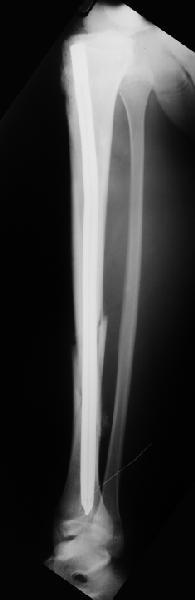

Вчера первый раз синтезировали голень гвоздем Fixion.

Спиральный оскольчатый перелом, ниже середины, у молодого парня. Сделали "классический" вариант гвоздя, который еще без винтов. Получилось все легко. Не торопясь, сделали операцию минут за 20. См. фото.

В отношении ранней нагрузки при спиральных переломах лучше не торопиться. По данному случаю необходимо достигнуть исчезновения щели между штифтом и внутреним кортексом по Rg. А так картинка прекрасная - и длина сегмента и репозиция. Можно поздравить, коллега!